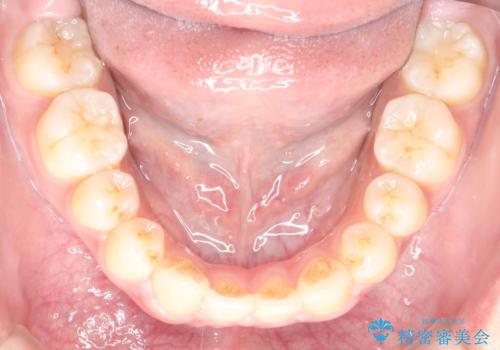

- 口元を引っ込めたいとのことで来院されました。

口元の突出感がありと、下顎の前歯が1本欠損していました。

上顎の前から両側の前から4番目の歯と、下あごの前歯を1本抜歯して、口元をすっきりさせる計画としました。